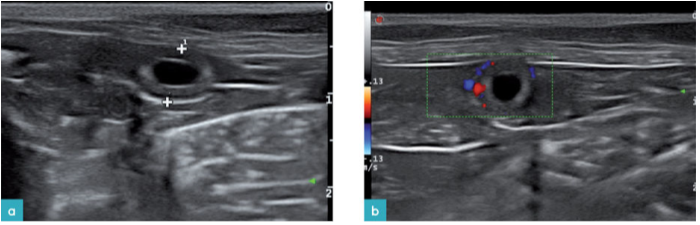

在一近期的研究中,使用高频探头对妊娠11天的母猫进行检查发现,子宫内已可见胎囊的影像,其表现为一直径1.2(士0.1)mm的无回声腔状结构。胎囊的形态随着发育过程不断变化,妊娠第15天时胎囊的平均直径约为5.3(±0.6)mm (图7.视频1)。

妊娠期第16天超声影像上可见胚胎,是在子宫腔的胎囊内的高回声结构。妊娠期的第16~18天可识别胎儿心脏、第16~20天可探知胎儿心率,第20天的心率为227土3次/每分钟(bpm)。此后胎儿心率逐渐下降,至妊娠期第40天时心率平均值变为2241次/每分钟,第60天心率降至223±7bpm。脐动脉和胎儿主动脉在妊娠20天是可见,颈总动脉和肾动脉分别在妊娠的第30天和第40天可见。